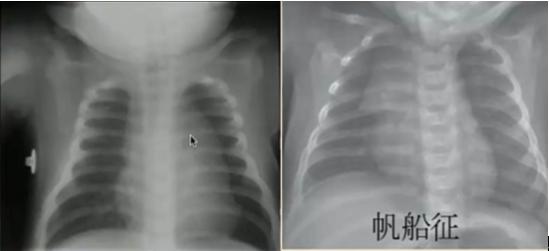

小儿胸腺位前纵隔内、心脏上方、胸骨后的软组织密度影,注意勿误认为纵隔或肺部肿块,一般3~4岁之后开始消退。在新生儿急性疾病时,胸腺可暂时消退,治疗后重新长回。

图3.小儿胸腺影的胸片表现(右侧胸腺表现:帆船征)